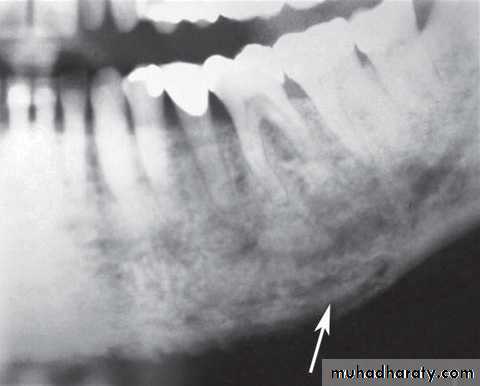

Radiographic features: Similar to chronic osteomylitis.

Location: posterior part of the mandible.

Periphery: ill – defined , irregular cortical resorption.

Main radiographic features:

Ragged, patchy or moth-eaten radiolucent areas of bone destruction.

• Occasional evidence of radiopaque sequestra of dead bone.

• Little evidence of healing.

Effects on surrounding structures: Stimulation of sclerosis. No new periosteal bone formation.

Extraction of /6, showing the typical destructive appearance (solid arrow),

resulting in a pathological fracture (open arrow). Radiotherapy had been given several years previously